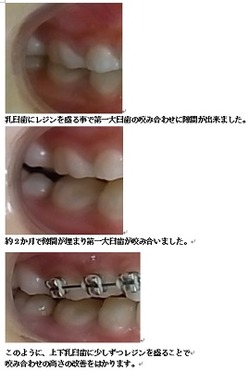

はじめに目立たないブラケット(歯に付ける矯正装置)を利用して上顎から歯並びを改善します。その折に同時にレジンを利用する事で咬み合わせの高さも挙上していきます。

☆受け口(反対咬合)の治し方(9歳3か月 女子 初診時)

咬み合わせの高さの改善をはかります。

一般的な反対咬合の症例です。当院では既成の矯正装置ではなくブラケットという矯正装置を歯に一本ずつ装着することで個人個人にあった治療をしていきます。当矯正歯科医院でのこどもの矯正の治療目標について